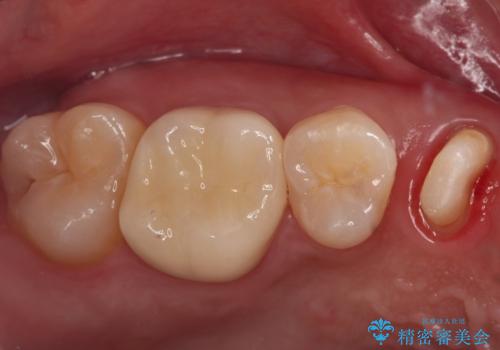

その後ラバーダムをして根っこの治療をし、被せ物を被せて治療終了となりました。

保険適用内だと抜歯の選択肢しかないような歯でも保険外の治療をすると残すことができる場合があります。

歯を抜かずに良い状態で保存できたことで大変喜んでいただけました。